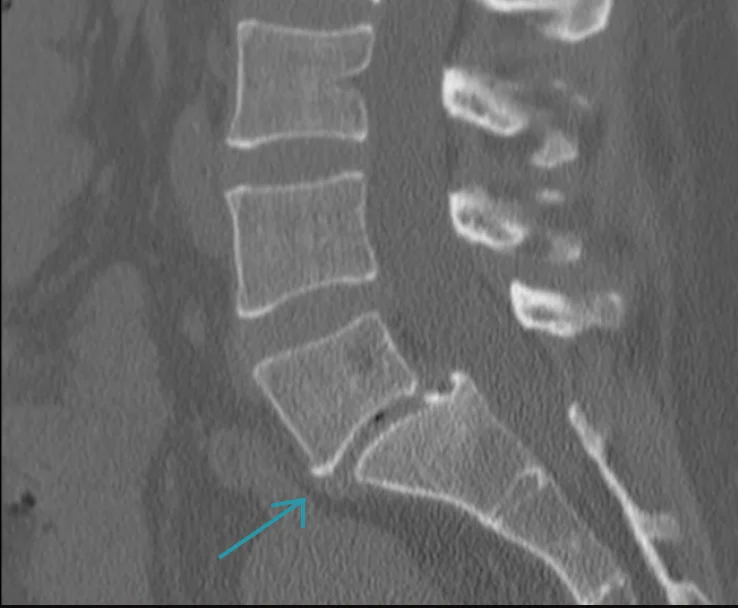

CT scan of the lumbosacral spine showing spondylolisthesis at L5–S1 with vertebral slippage

CT scan of the lumbosacral spine – spondylolisthesis at L5–S1. Courtesy of David Puyó Vera, Radiopaedia.org. Slučaj rID: 23567